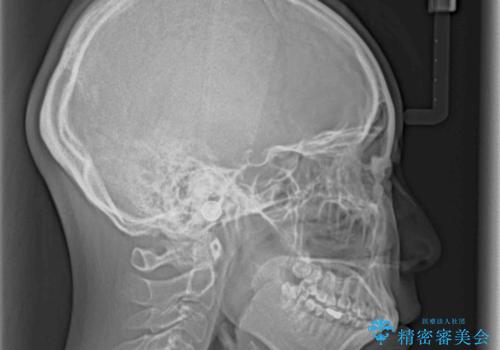

- 口元の突出感を気にして来院された患者様です。

上下左右の第一小臼歯4本を抜歯して口元を下げる治療計画としました。

目立たない装置が希望であったため、上顎が裏側装置である、ハーフリンガル装置を選択されました。